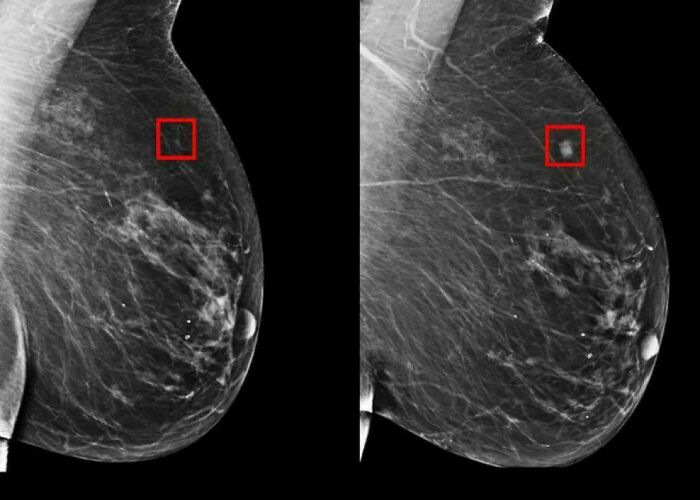

Artificial Intelligence Detects Breast Cancer 5 Years Before It Develops